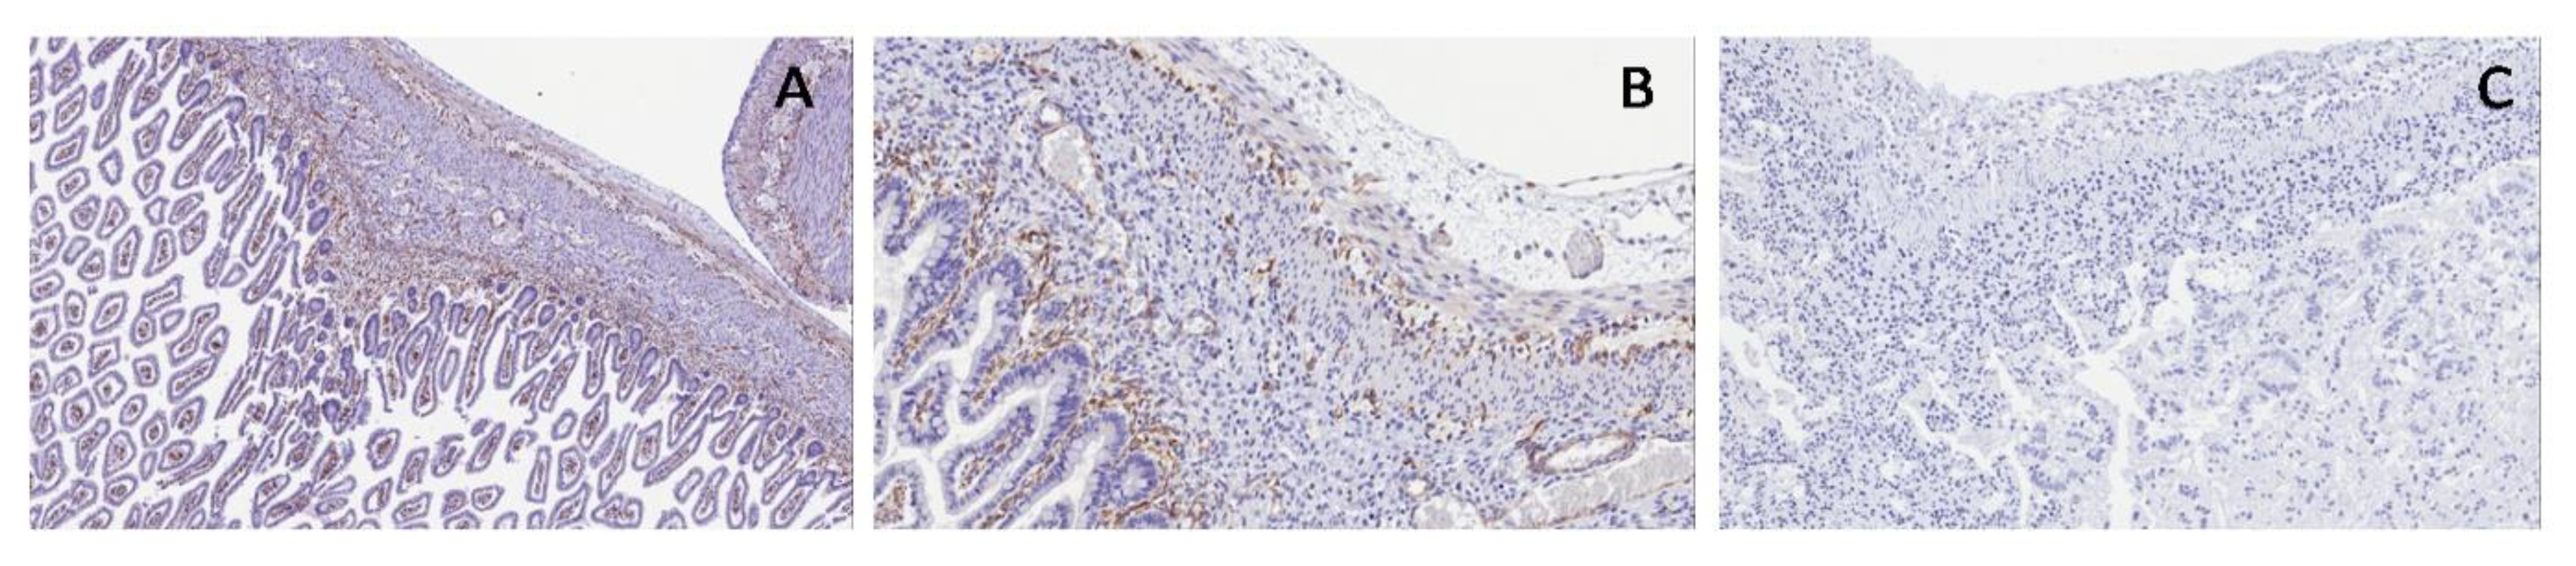

Bladder: SMA staining marked longitudinal and transversal muscular layers intersected by embryonal mesenchyme; nervous plexuses were evaluated with S100 protein, showing their arrangement among the muscular layers; WT1c was poorly marked in ganglion cells, neural cells and their cytoplasmic extensions (Figure 3).

Figure 3. Normal bladder. Immunohistochemical staining shows smooth muscular actin (SMA) (A) in longitudinal and transversal muscular layers, S100 (B) in nervous plexuses (arrow) among the muscular layers and WT1c in ganglion cells (arrow) and neural cells (C).